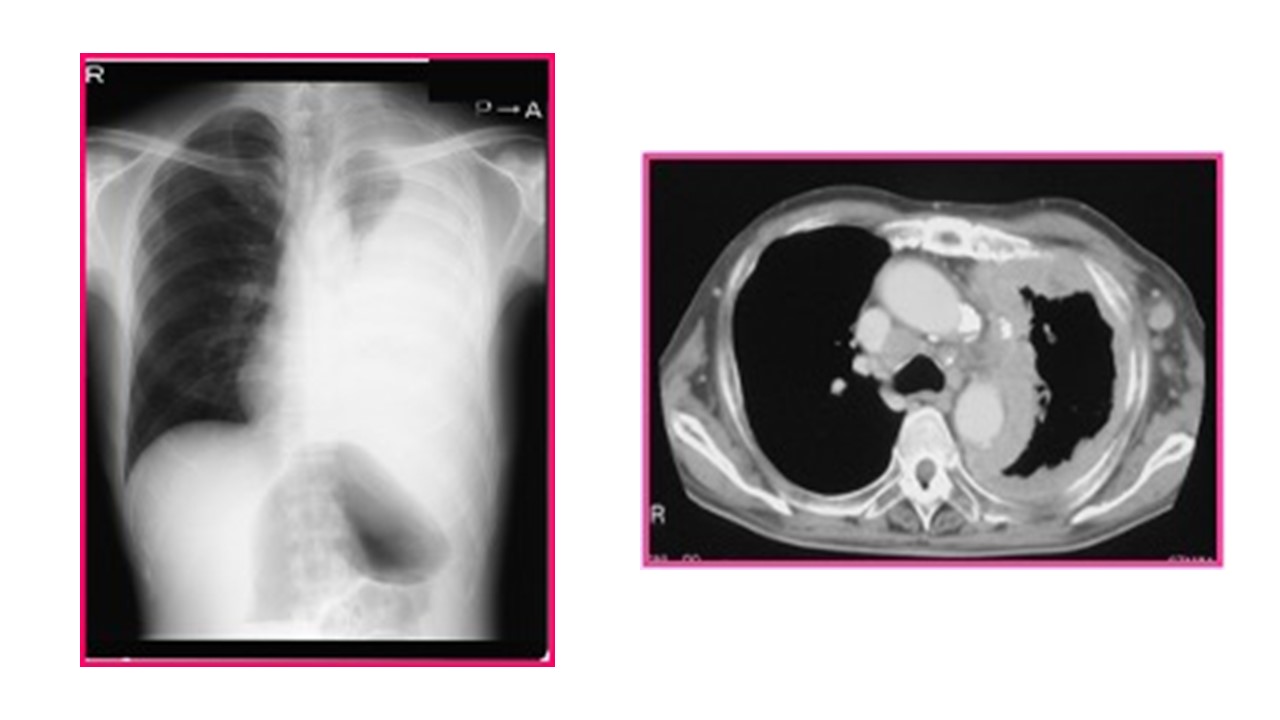

- 肺の胸膜肥厚

- 胸膜プラークと呼ばれるカルシウム沈着

- 胸水を示す可能性のある体液の蓄積